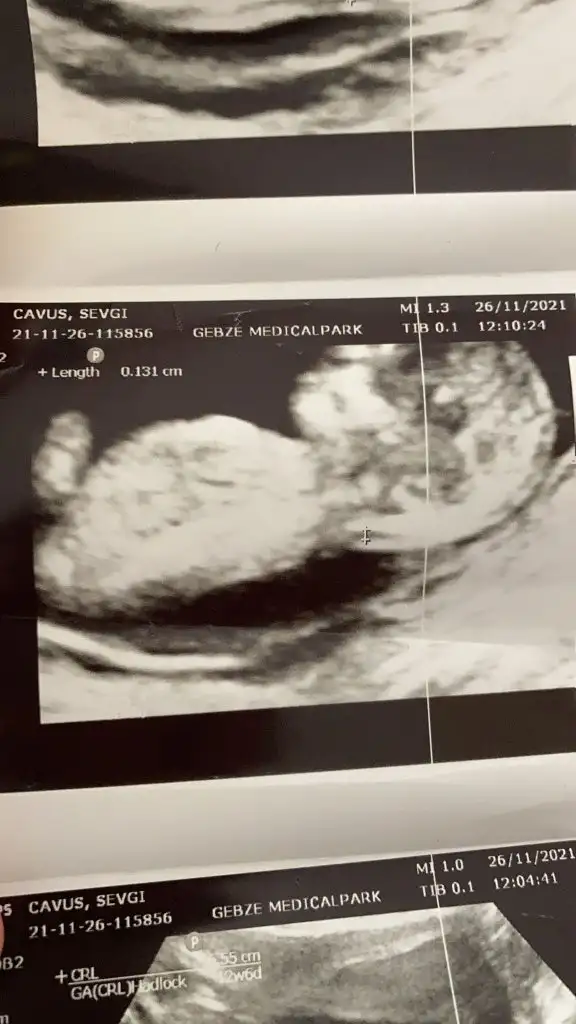

Doktor erkek gibi duruyor dedi ama bakalim net değilEmin olamadım kız gibi sanki

Canım bizde 13 haftalık olduk geldik bakar mısın

Doktor bir şey demedi

Erkek sankiİkra hanım merhaba 12 hafta görüntülerini ekledim sizce nedir cinsiyeti